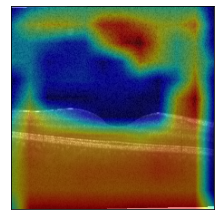

GradCAM

GradCAM

GradCAM

GradCAM

Fig 6, 7, 8 and 9 depicts the visualization of correct predictions by our proposed CNN model where fig 6 is class CNV, fig 8 is class DME, fig 7 is DRUSEN and finally, fig 9 is NORMAL. Here the first photo in every class is the original image. The LIME map of our suggested model’s prediction is shown in image B whereas in image C the positive region is highlighted in specific sections on the original image. For Image D we have increased the number of features from 5 to 10 thus more regions have been predicted as the positive region which is highlighted in green. After increasing the features from 5 to 10, some of the regions are predicted wrongly. The red regions represent the output of incorrect prediction. The following image represents the Grad-CAM heatmap highlighting the regions with our model’s prediction.